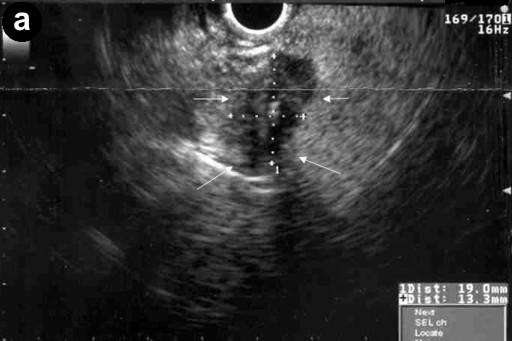

A 57-year-old man with a one year history of alcohol-induced chronic pancreatitis presented with a 1-month history of intermittent epigastric pain. He denied any associated nausea, vomiting, diarrhea, weight loss or other gastrointestinal symptoms. His past medical history was significant for hypertension, type 2 diabetes mellitus, dyslipidemia and chronic obstructive pulmonary disease. The abdomen was soft and non-tender. The liver and spleen were not felt, and no abdominal mass was appreciated. His physical examination was otherwise unremarkable. Laboratory evaluation revealed serum amylase of 356 U/L (reference range: 30-111 U/L) and a lipase of 679 U/L (reference range: 46-218 U/L). Complete blood counts, liver chemistries, carbohydrate antigen 19-9, and alpha-feto protein levels were all normal. Pancreas protocol CT scan of the abdomen revealed a 8x5 cm cystic fluid collection in the left liver lobe, an L-shaped subcapsular fluid collection inferior to right hepatic lobe 10x9 cm in size and a 2.4 cm complex fluid accumulation that involved the head and the superior aspect of the body of pancreas (Figure 1). CT guided diagnostic aspiration of the hepatic cystic lesion drained 100 mL of straw-colored fluid which showed no organisms on gram stain and was sterile on bacterial and fungal cultures. Cytological examination of the fluid did not reveal any malignant cells. The amylase level in this fluid was greater than 51,065 U/L which confirmed the diagnosis of intrahepatic pancreatic pseudocyst extension. At the time of CT guided aspiration, the pseudocyst was treated with percutaneous drainage with the placement of an 8F pig-tail catheter. The intrahepatic pancreatic pseudocyst extension failed to resolve even after 4 weeks of the pig-tail catheter placement (Figure 2). At this point, an ERCP was performed which revealed a normal cholangiogram. Pancreatography revealed a normal-appearing main pancreatic duct to the region of the pancreatic neck, and a ductal stenosis 12 mm in length was identified beginning at the pancreatic body near the neck. The main pancreatic duct and pancreatic duct branches were dilated upstream of the stenosis to about 7 mm (Figure 3). After performing an 8 mm ventral pancreatic sphincterotomy; the stricture was dilated with a 6 mm biliary dilating balloon and a 7F, 10 cm long pancreatic stent was inserted to the tail (Figure 4). Brush cytology and intraductal biopsy specimens were obtained from the stricture and revealed fibrosis and changes of chronic pancreatitis; they were negative for malignancy. EUS examination revealed a pancreatic head cystic lesion extending into the left hepatic lobe (Figure 5ab); fluid examination revealed an amylase of 54,450 U/L and the cytology was negative for malignancy. A follow-up pancreas protocol CT of the abdomen 6 weeks later revealed complete resolution of the pancreatic head fluid accumulation and the intrahepatic pancreatic pseudocyst and decrease in size of the L-shaped subcapsular fluid collection to 2x4 cm (Figure 6). Percutaneous drainage of the remaining L-shaped subcapsular fluid collection was discussed with the patient but he refused any percutaneous or surgical drainage. A follow-up pancreatogram revealed marked improvement in the pancreatic duct stricture. He remains asymptomatic after 9 months of follow-up.

Figure 5. a. EUS showing the pancreatic head cystic lesion. b. Cystic lesion extension into the left hepatic lobe. |